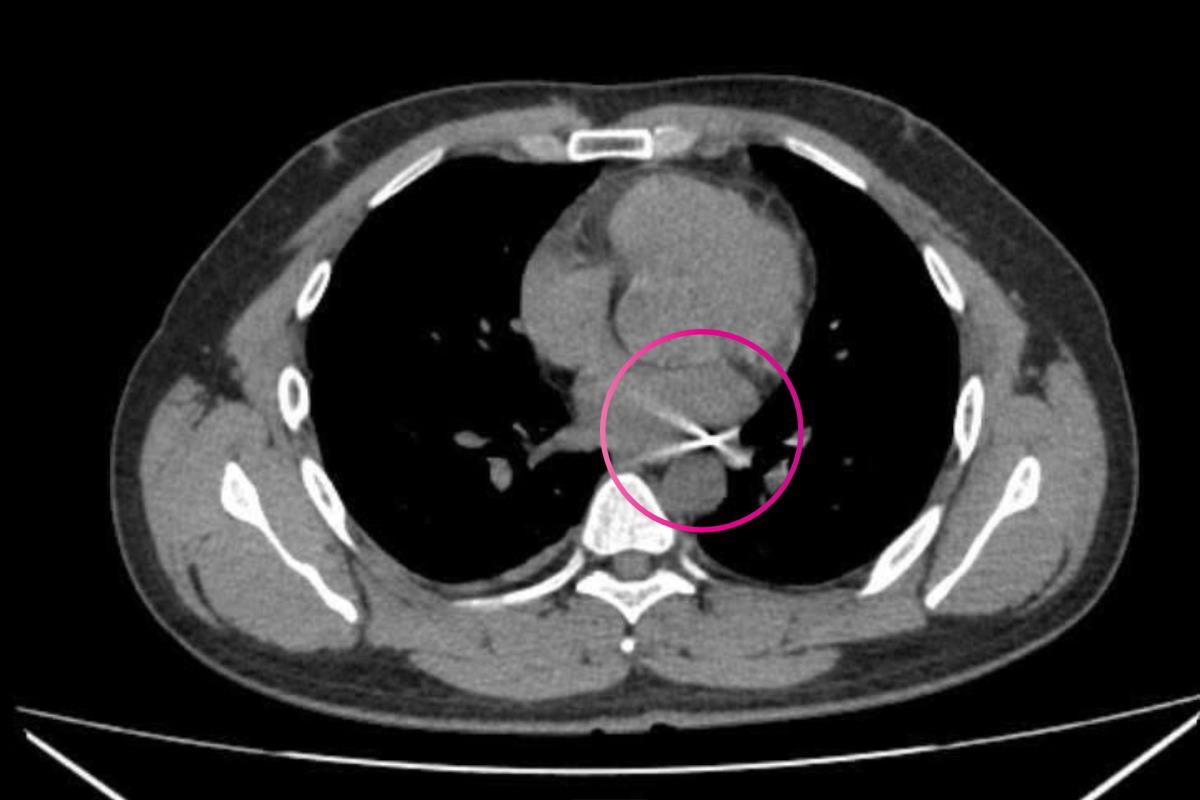

Qua thăm khám, các bác sĩ xác định bệnh nhân bị viên đạn đâm từ sau lưng bên phải xuyên sang bên trái, với đường đi cực kỳ hiểm hóc, áp sát nhiều cấu trúc sinh tử trong lồng ngực.

Quá trình tìm kiếm, các bác sĩ phát hiện đầu đạn có kích thước khoảng 0,3 x 0,5 cm, mắc kẹt tại vị trí góc giữa động mạch chủ và động mạch phổi. Sau hơn 4 giờ phẫu thuật, ca mổ thành công.

Theo các bác sĩ trực tiếp thực hiện ca phẫu thuật, dù đầu đạn có kích thước nhỏ nhưng chỉ cần lệch vài milimet hoặc bỏ sót trong quá trình kiểm tra, nguy cơ tổn thương tim, mạch máu lớn là rất cao, có thể dẫn đến tử vong./.